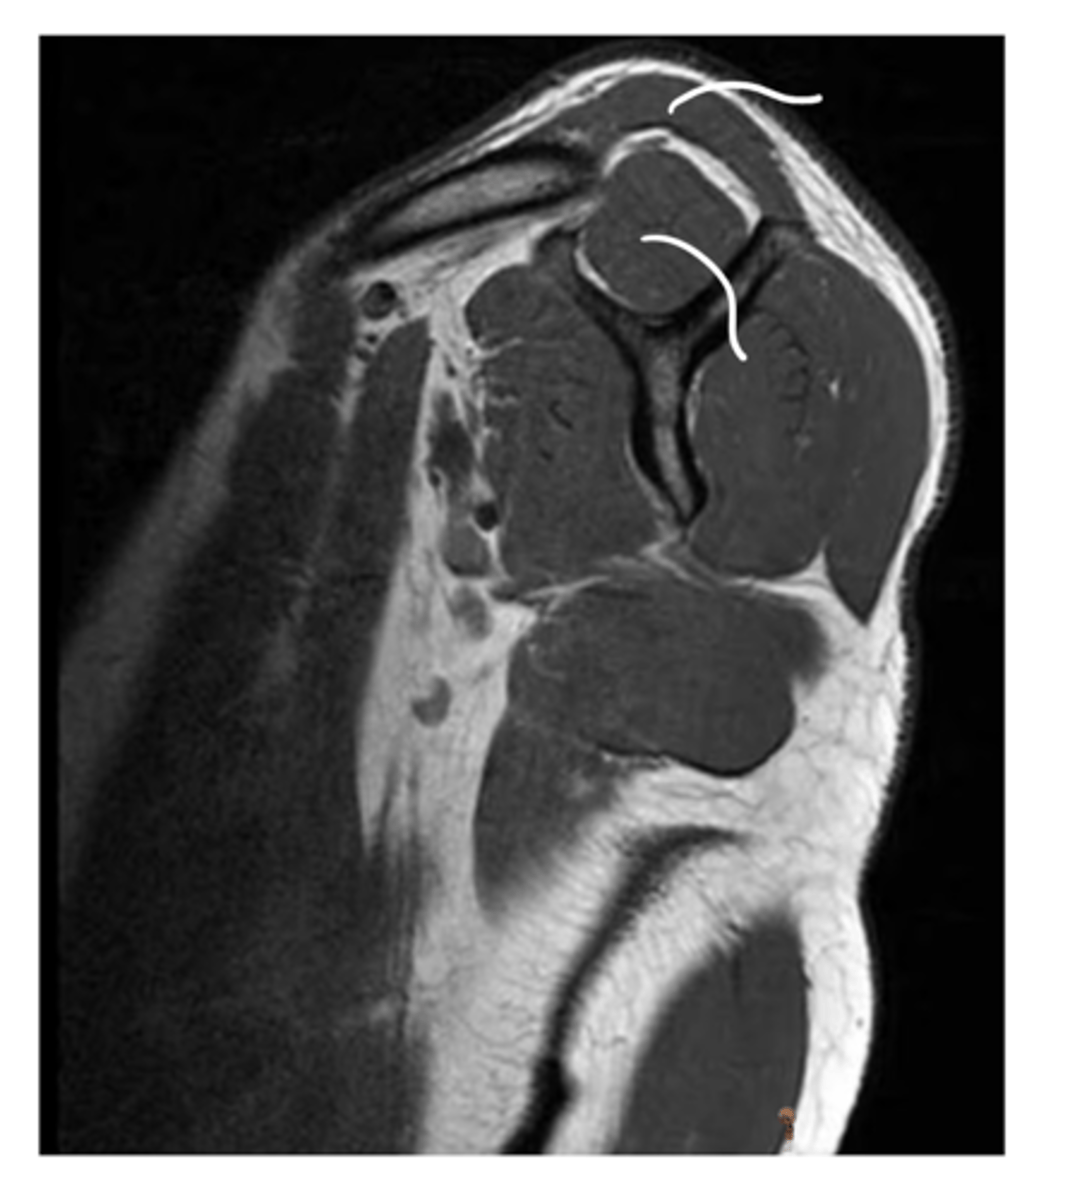

An axial view of the supraspinatus tendon fibers wrapping around the head of the humerus

What is this image depicting?